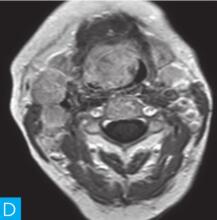

喉咽部MRI检查:病人采取仰卧位,横断位扫描为主,包括T1WI、T2WI及T2WI脂肪抑制序列,扫描范围自鼻咽部至喉咽以下,扫描层厚为3.5mm、层间隔0.35mm,矩阵512×512;辅以冠状位T2WI,矢状位T2WI序列及脂肪抑制序列,平扫后行横断位、冠状位及矢状位的增强扫描,造影剂量0.2ml/kg。见图1。

图1 咽喉部MRI:A.喉咽部MR横断面平扫T1WI;B.喉咽部MR横断面T2WI;C.喉咽部MR横断面T2压脂;D.喉咽部MR横断面增强T1WI;E.喉咽部MR冠状面T2WI;F.咽喉部MR冠状面增强T1WI

MRI平扫可见右侧扁桃体较大的软组织肿块,T1WI呈稍低信号,T2WI呈稍高信号,信号较均匀,T2WI压脂序列上呈高信号,病变与右侧咽扁桃体及舌根部分界不清,左侧咽扁桃体肿大,口咽腔明显变形狭窄,病灶延伸至喉前庭;双侧锁骨上窝及颈血管鞘周围间隙内可见多发大小不等的肿大淋巴结,大部分肿大淋巴结信号较均匀,呈稍高信号,边界清楚,右侧颈部间隙内个别肿大淋巴结内见少量斑片状液化坏死区;增强扫描后下咽部病变及双侧颈部间隙内的肿大淋巴结均呈明显的较均匀强化,提示该两处占位病变的血供较为丰富,且可能为同源性病变,因此采取“一元论”诊断思维进行分析更为合理。

(1)发现病变与认证:扁桃体及颈部病变较为容易发现,主要是分析两方面:一是仔细观察咽部有无原发病变,原发病变的形态及信号;二是评价淋巴结的分布,淋巴结的信号及生长特点。本病例基本征象为扁桃体病变信号均匀,无坏死,颈部淋巴结分布广泛,信号均匀。

(2)定位诊断:对于本病例来说,发现两处病变,包括咽部和颈部。咽部的病变位于扁桃体,延伸至喉咽腔,口咽腔和梨状窝受压变窄。颈部的病变为多发淋巴结增大,淋巴结广泛分布于Ⅱ~Ⅴ区。

本病例的特点为右侧扁桃体肿块,病变边界较清楚,表面光滑,信号均匀。双侧颈部间隙内多发肿大淋巴结,淋巴结围绕颈动脉鞘,部分病变融合倾向,广泛分布于Ⅱ~Ⅴ区,增强后病变较明显强化。

该病例首先对病变进行定位,包括咽部的和颈部的。咽部的病变:病变位于扁桃体,延伸至喉咽腔,口咽腔和梨状窝受压变窄(引起异物感和吞咽困难的原因)。颈部的病变:多发淋巴结增大,淋巴结广泛分布于Ⅱ~Ⅴ区。扁桃体病变的信号特征:扁桃体病变表面光滑,提示黏膜完整,病变来源于黏膜下,病变信号均匀,无坏死,进一步支持病变来源于黏膜下。颈部淋巴结病变的特征:淋巴结分布广泛,信号均匀(可以初步排除结核和转移,后两者容易坏死),围绕颈动脉鞘,但是不侵犯颈动脉鞘(转移容易侵犯颈动脉鞘),部分淋巴结融合倾向(结核淋巴结增大,无融合倾向,而且容易坏死),病变中度强化,进一步支持颈部淋巴瘤的诊断。诊断原则:首先仔细观察咽部有无原发病变,原发病变的形态及信号,尤其黏膜是否完整。其次评价淋巴结的分布,淋巴结的信号及生长特点。